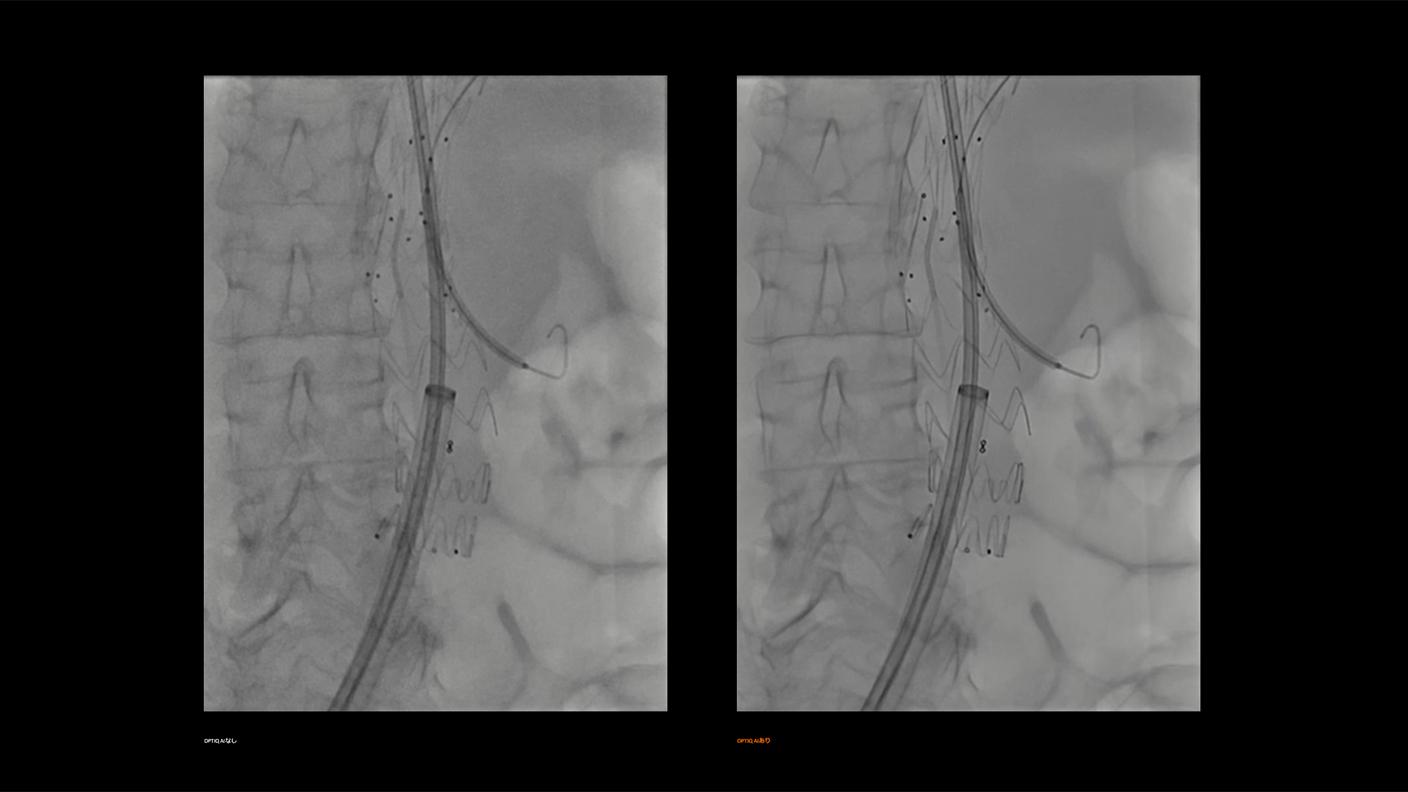

AIを用いた画像処理技術「OPTIQ AI」による高画質・低被ばく撮影

AIを用いた画像処理技術「OPTIQ AI」は、画像生成プロセスにおいてノイズを大幅に抑制し、高精細かつ高コントラストな画像を実現します。

CNR(コントラストノイズ比)をベースとした画像処理により、システム条件や患者さんの体格差、Cアームの角度などに影響を受けない、安定した画像を提供します。また、AIを活用した高度なアルゴリズムにより、幅広い2D透視・撮影モードおよびさまざまな部位において、信号強度を維持したまま量子ノイズおよび電子ノイズをリアルタイムで低減します。X線散乱や装置由来のノイズを抑制することで、微細な血管やカテーテル、ガイドワイヤーなどの治療デバイスを明瞭に描出し、良好な視認性を確保します。